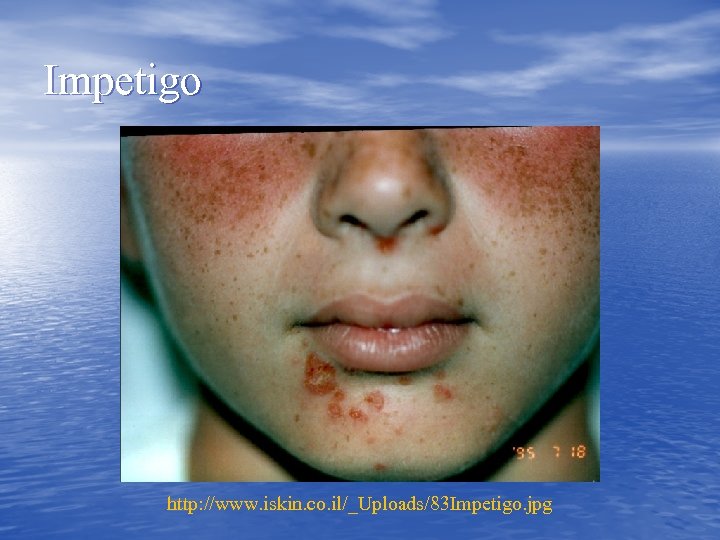

Impetigo http: //www. iskin. co. il/_Uploads/83 Impetigo. jpg

Impetigo http: //www. iskin. co. il/_Uploads/83 Impetigo. jpg